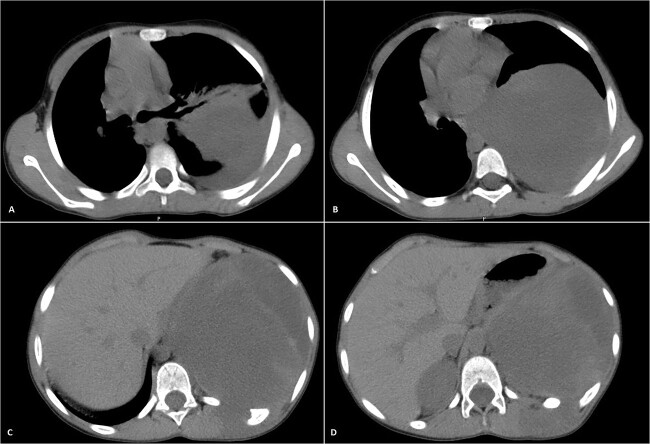

His postoperative course was uneventful. A chest CT was performed following the surgery, and the results revealed that the previous left lung mass had been completely removed without definite residue (Fig. 4). The patient is on close follow-up monthly with a physical exam, chest X-ray, and chest CT every 3–6 months. For the past two years, there have been no discernible clinical or radiological indicators of recurrence (Fig. 5).

Figure 4.

Selected axial cuts of the patient’s chest–lung window. The previously mentioned left posterior chest wall mass is no longer seen with post-operative changes noted.